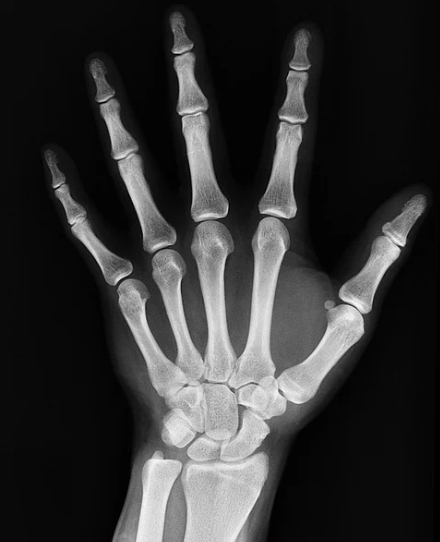

뼈에 금이 갔을때 증상

뼈란 간단하게 말하면 골격을 이루는 가장 단단한 조직 중하나로 전신에 걸쳐 분포되어 있습니다. 이러한 뼈는 구조적으로 몸의 형태를 유지하고 내부 장기를 보호해 주며 근육 작용의 지렛대 역할을 하는 등 우리몸에서 아주 중요한 일부 중 하나입니다. 그럼 이러한 뼈에 금이 갔을때 증상에 대해 알아 보도록 하겠습니다.